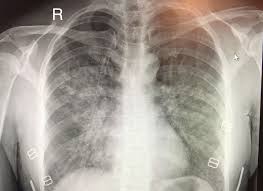

바로 진료(응급 포함)가 필요한 위험 신호

아래 증상은 “오늘은 좀 쉬면 괜찮겠지”로 버티기보다, 즉시 평가가 필요한 경우가 많습니다.

- 숨이 갑자기 심하게 차서 말을 잇기 어렵다

- 거품 가래가 나오거나 피가 섞여 나온다

- 가슴 통증이 강하거나 식은땀·실신 느낌

- 입술/손끝이 파래지거나 의식이 멍해짐

- 고열·오한, 옆구리 통증이 함께 나타남